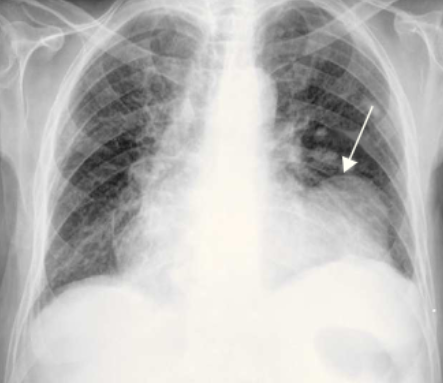

A radiografia de tórax costuma ser normal ou apresentar discreto aumento da área cardíaca, uma vez que, na ruptura de parede livre, o derrame pericárdico geralmente se instala de forma aguda. Alterações mais evidentes na silhueta cardíaca ficam mais evidentes em situações de instalação insidiosa do derrame pericárdico.

Ragiografia de tórax, evidenciando pseudoaneurisma (seta branca):